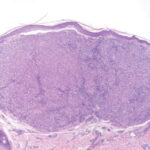

Histopathology of Nodular Melanoma and Common Vertical Growth Phase (Tumorigenic Melanoma) Architectural Features. In a typical tumorigenic melanoma, there is contiguous proliferation of neoplastic melanocytes in the dermis forming a tumor mass that is larger (usually much larger) than the largest nest in the |

Perhaps the best-known single criterion for melanoma is the upward pagetoid extension of tumor cells into the epidermis overlying the melanoma. However, this pagetoid melanocytosis or pagetoid spread is not specific for melanoma (152). Although in nodular melanoma, permeation of the epidermis with tumor cells may be absent or may be limited to that portion overlying the dermal tumor, lateral extension of melanoma cells in the epidermis and papillary dermis beyond the confines of the dermal tumor is seen in the adjacent nontumorigenic compartment of complex primary melanomas [SSM, LMM, acral-Ientiginous melanoma (ALM)]. This phenomenon greatly aids in histologic recognition of these tumors, and, conversely, the recognition of nodular melanomas, which lack this adjacent component, may be difficult. For this reason, nodular melanoma may be difficult or impossible to distinguish from a metastatic melanoma in the skin, and when such a tumor is amelanotic, the distinction from other cutaneous neoplasms may be impossible without immunohistochemistry. |